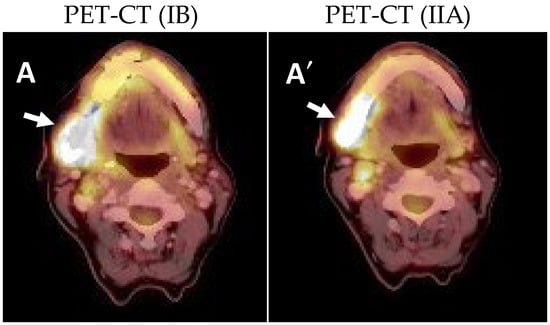

4.3. Positron Emission Tomography-Computed Tomography